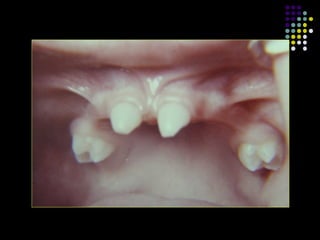

Impactacion

 Pseudoanodoncia.

 Frecuente.

 3ros molares inferiores y caninos superiores.

 Es raro en incisivos y primeros molares.

 Obstruccion producto de apinamiento.

 Ocasionalmente debido a una via de

erupcion anormal, orientacion inusual del

germen.

 Otra causa puede ser la Anquilosis.